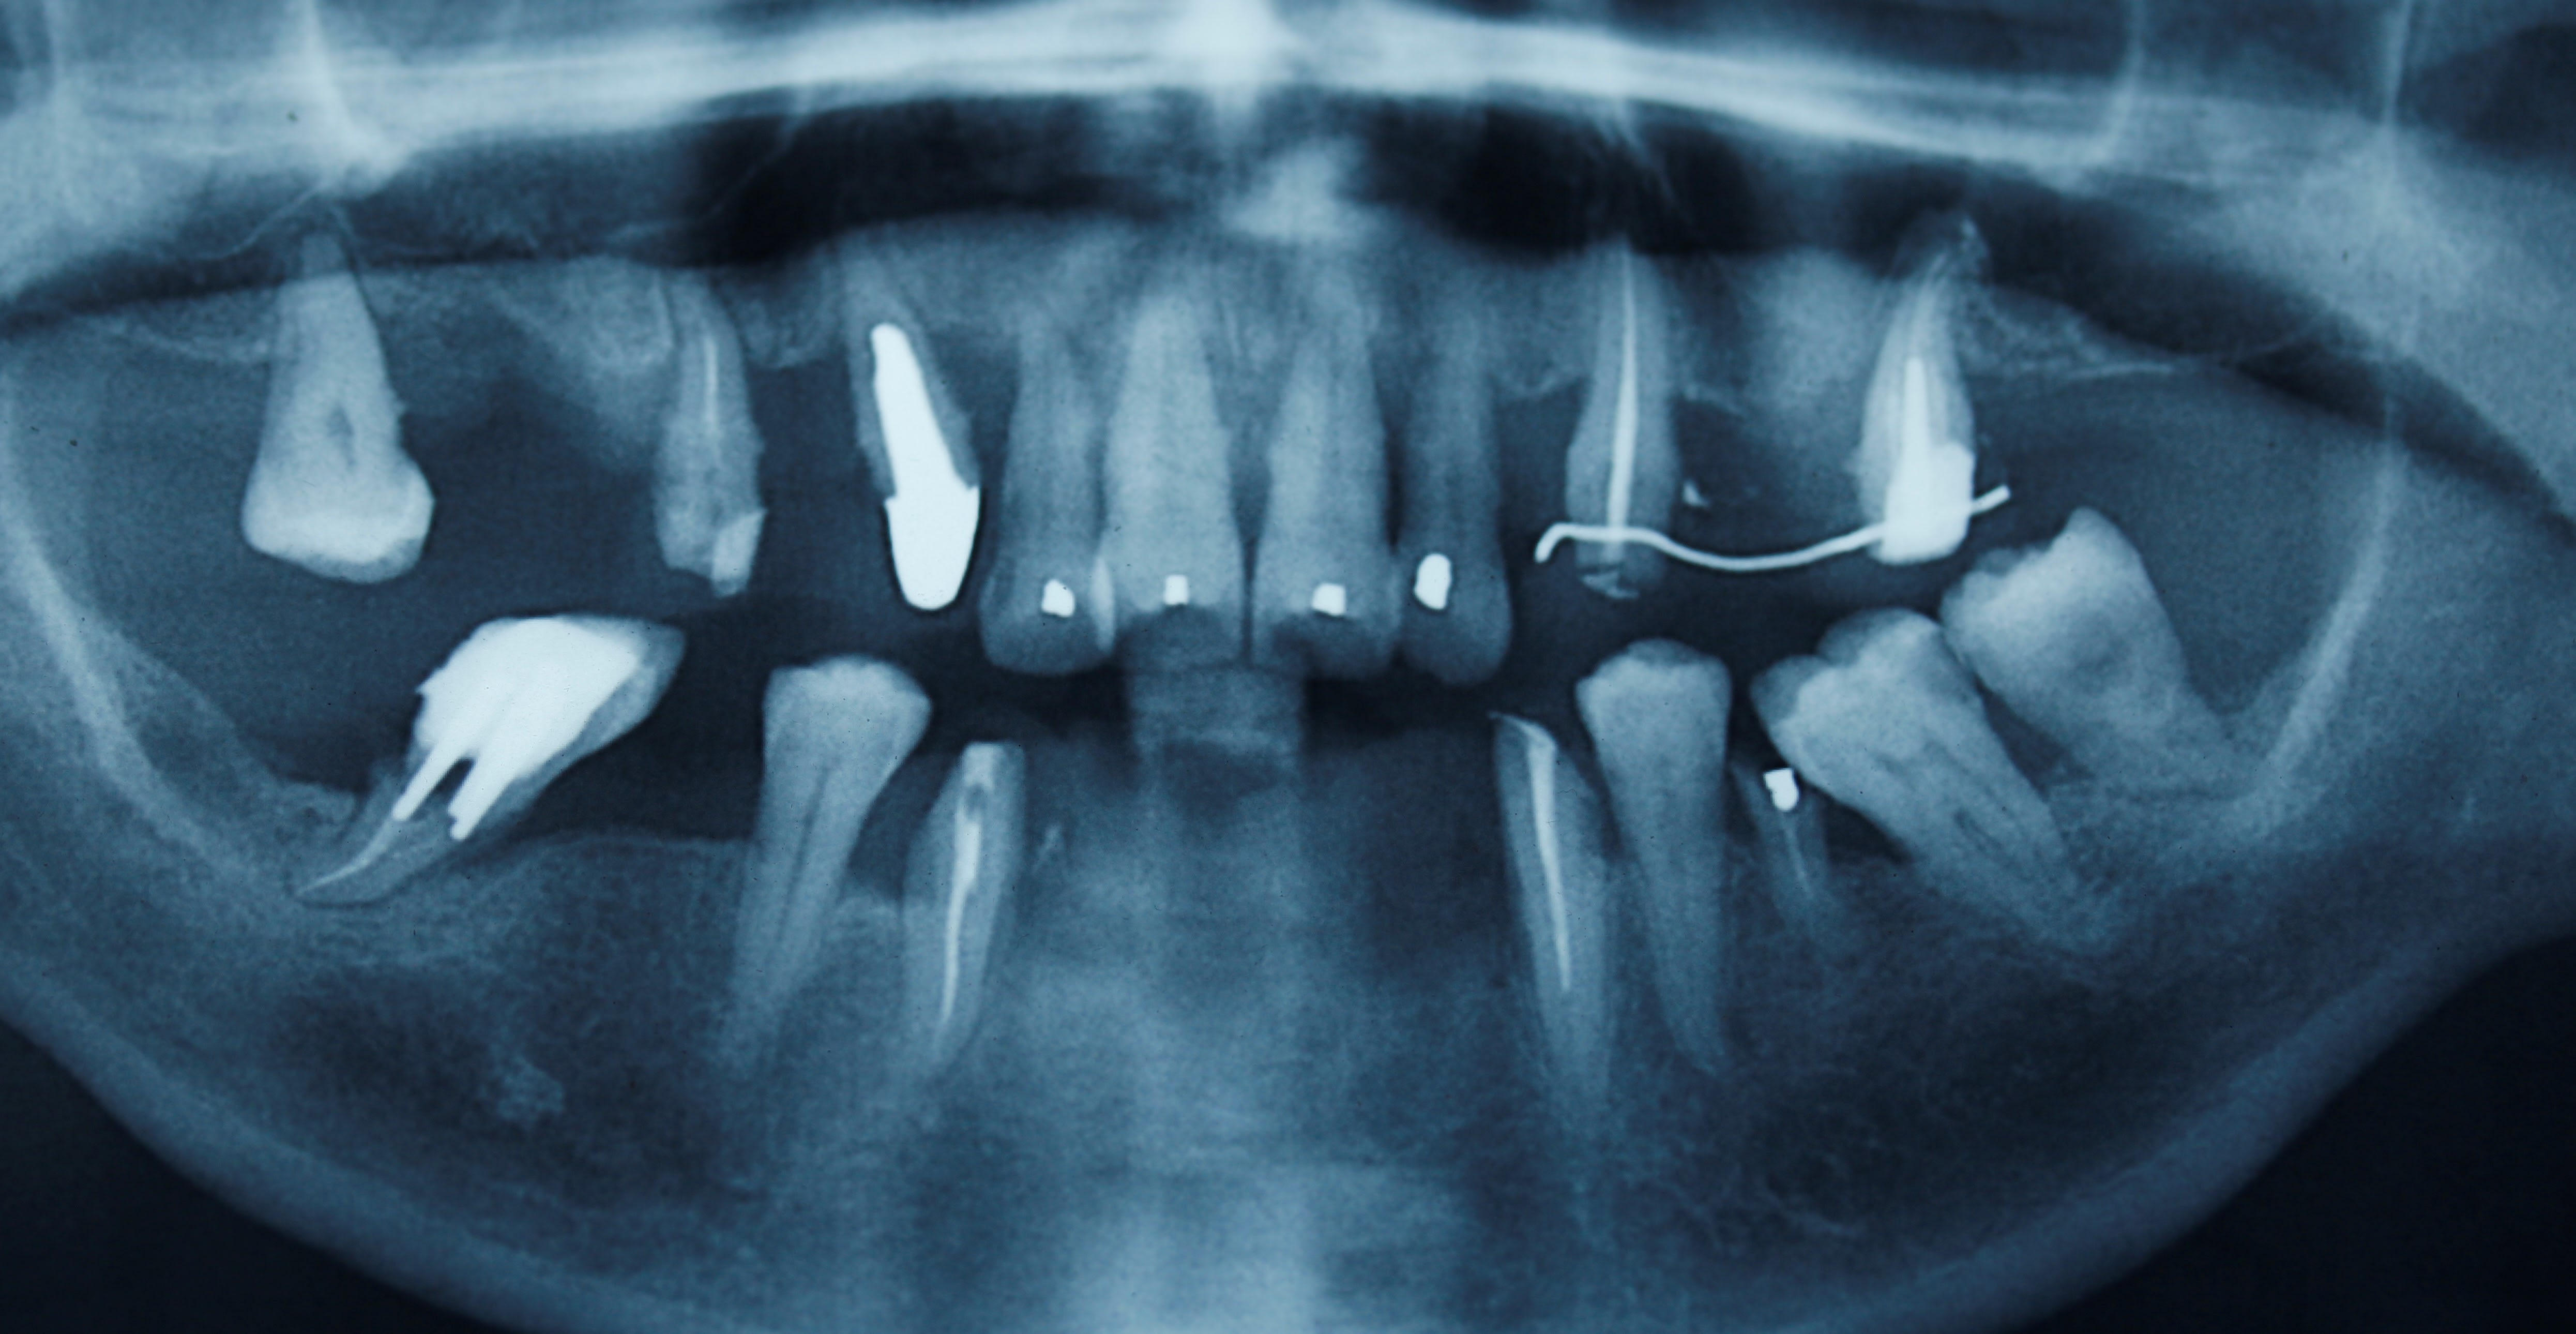

et la pano , de 2008 2 ans avant le debut du chantier , des reprises de ttt , et extractions

mg 1953 nnmy5t - Eugenol

un pb endo venant de la canine ? peut être . possible , si tu vois la pano d avant les reprises ç est affolant .